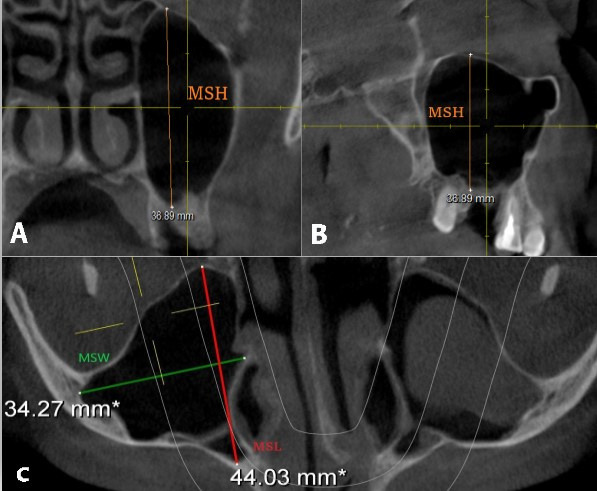

Materials and methods: This retrospective descriptive study analyzed 200 CBCT scans, comprising 400 maxillary sinuses from patients treated at the Faculty of Dentistry University of Sarajevo. The study assessed sinus dimensions, volumes, anatomical features, their relationships with adjacent anatomical structures, and the occurrence of pathological alterations. Furthermore, the patient's gender and dental status were studied in relation to these features. The sinus measurements were performed with Sidexis 4 software (Dentsply Sirona, Germany), which is intended for precise linear measurements in three orthogonal planes.

Results: Significant differences were found in sinus width between patients with full dentition and those with partial or complete edentulism (p<0.01). Male participants exhibited larger mean sinus dimensions compared to females in all dimensions. The maxillary sinus floor was inferior to the nasal floor in 91.5% of cases. Various types of sinus membrane abnormalities were observed, with normal membrane thickness in 53.75% of cases. Sinus septa were most frequently located on the roof of the sinus, and their frequency varied significantly among patients with different dentition statuses. The study also identified 274 Haller cells and documented several pathological changes, with mucosal thickening exceeding 3 mm being the most common alteration.